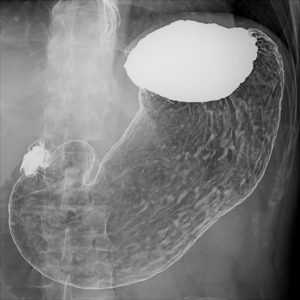

健診:胃バリウム

発泡剤(顆粒薬)5gとバリウム(液体薬)150mlを飲用して胃の撮影を行います。

発泡剤は溶けると炭酸ガスを発生させてガスで胃・食道をふくらませます。胃がふくれるのでゲップが出やすくなります。

ゲップを出してしまうと胃がしぼみ胃壁の観察が難しくなります。ゲップが出そうになったらツバを飲み込んで我慢して頂きます。

バリウムを飲み終わったら寝台を水平に倒します。右回りで身体を軸にして回転を複数してもらい胃壁にバリウムを付着して撮影を行います。

角度や方向を変えて12~14回程度の撮影を行います。撮影をする度に、バリウムを付着させるために右回転をしてもらい撮影を行います。

胃は十二指腸へバリウムが流れると発泡したガスも無くなります。胃がしぼんだら発泡剤を追加飲用して撮影を行います。